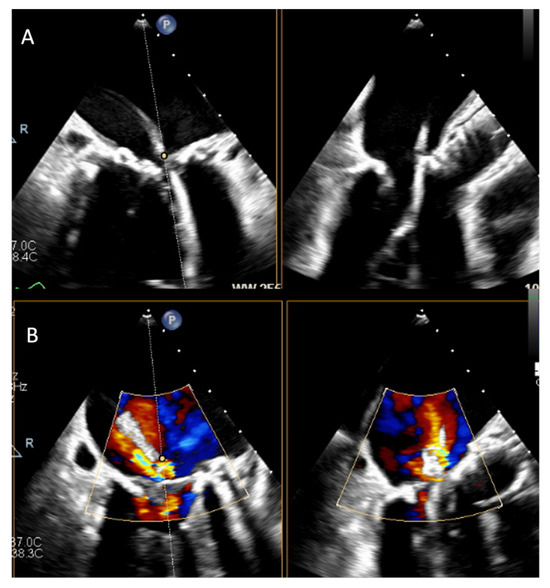

Background and clinical significance. Valve-in-ring (ViR) transcatheter mitral valve replacement (TMVR) is an established therapeutic option for patients with failed surgical mitral valve repair at high surgical risk. Left ventricular outflow tract (LVOT) obstruction and prosthesis-related complications are well described, but other [...] Read more.

Background and clinical significance. Valve-in-ring (ViR) transcatheter mitral valve replacement (TMVR) is an established therapeutic option for patients with failed surgical mitral valve repair at high surgical risk. Left ventricular outflow tract (LVOT) obstruction and prosthesis-related complications are well described, but other postprocedural findings remain poorly characterized. Case presentation. We report a challenging case of a persistent LVOT mass following ViR TMVR. A 78-year-old man underwent transapical ViR TMVR with a Sapien 3 valve for mitral stenosis. Early post-procedural echocardiography showed normal prosthetic function and no LVOT obstruction. During inpatient cardiac rehabilitation, transthoracic echocardiography revealed a mobile mass in the LVOT. The patient did not show any clinical, microbiological, or laboratory evidence of infection. Blood cultures were negative, and the mass showed no changes despite anticoagulation. Two- and three-dimensional transesophageal echocardiography demonstrated a mobile structure attached to the mitral prosthetic ring by a thin peduncle. After a comprehensive multimodality assessment, thrombus and infective endocarditis were considered unlikely. The mass was ultimately interpreted as a displaced remnant of the native anterior mitral leaflet. Given the prohibitive surgical risk and absence of complications, conservative management with echocardiographic follow-up was adopted. Conclusions. This case study emphasizes the role of advanced echocardiography and multimodality analysis in avoiding misdiagnosis and inappropriate therapeutic interventions. Full article

Show Figures

Figure 1